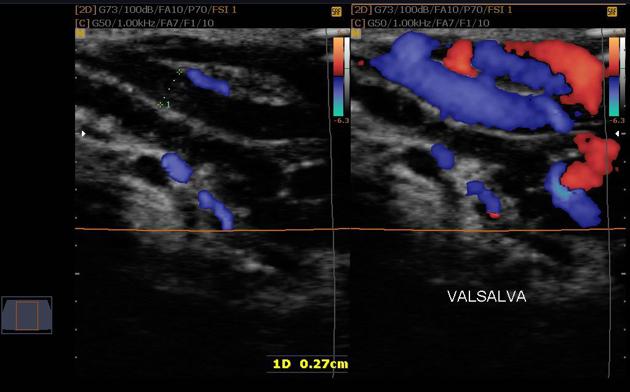

- Siêu âm Doppler màu xác định có giãn tĩnh mạch thừng tinh phải có 2 tiêu chuẩn chính:

Có ít nhất một tĩnh mạch có đường kính trên 2mm.

Có hồi lưu tĩnh mạch khi thực hiện nghiệm pháp Valsalva.